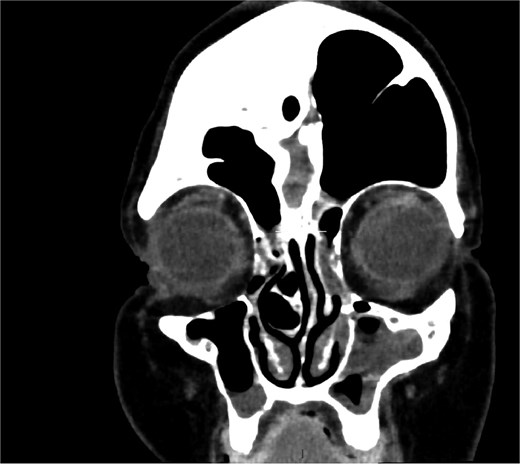

MRI demonstrated marked expansion of the left frontal sinus, consistent with PD, exerting a mass effect on the adjacent left frontal lobe and associated with a small area of increased T2-FLAIR signal intensity (Fig. 1). There was no evidence of compression of the lateral ventricle. However, mild prominence of the sulci and lateral ventricle on the left side suggested underlying parenchymal volume loss. No signs of hydrocephalus, midline shift, restricted diffusion, or susceptibility artifacts were identified. The optic nerve, optic chiasm, and optic tracts appeared normal. CT tomography confirmed these findings (Figs 2 and 3).

Coronal CT showing volume loss in the left hemisphere and enlarged sinus.